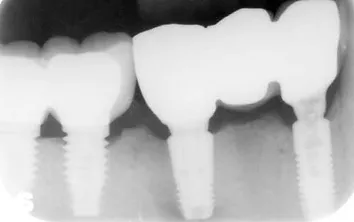

Fixed prosthodontics are either crowns or bridges which are cemented onto the tooth or teeth permanently. A crown is applied to protect either a heavily restored tooth or a root canal treated tooth. The tooth has to be prepared and reduced in size. An impression is then taken, and a temporary crown used until the permanent crown has been made. We have a Cerec Machine in which crowns can be made within just 48 hours.

A Bridge utilises the neighbouring teeth to support a missing tooth. This procedure may be used when dental implants are not suitable, and when the neighbouring teeth are heavily restored and are strong enough to support the missing one.